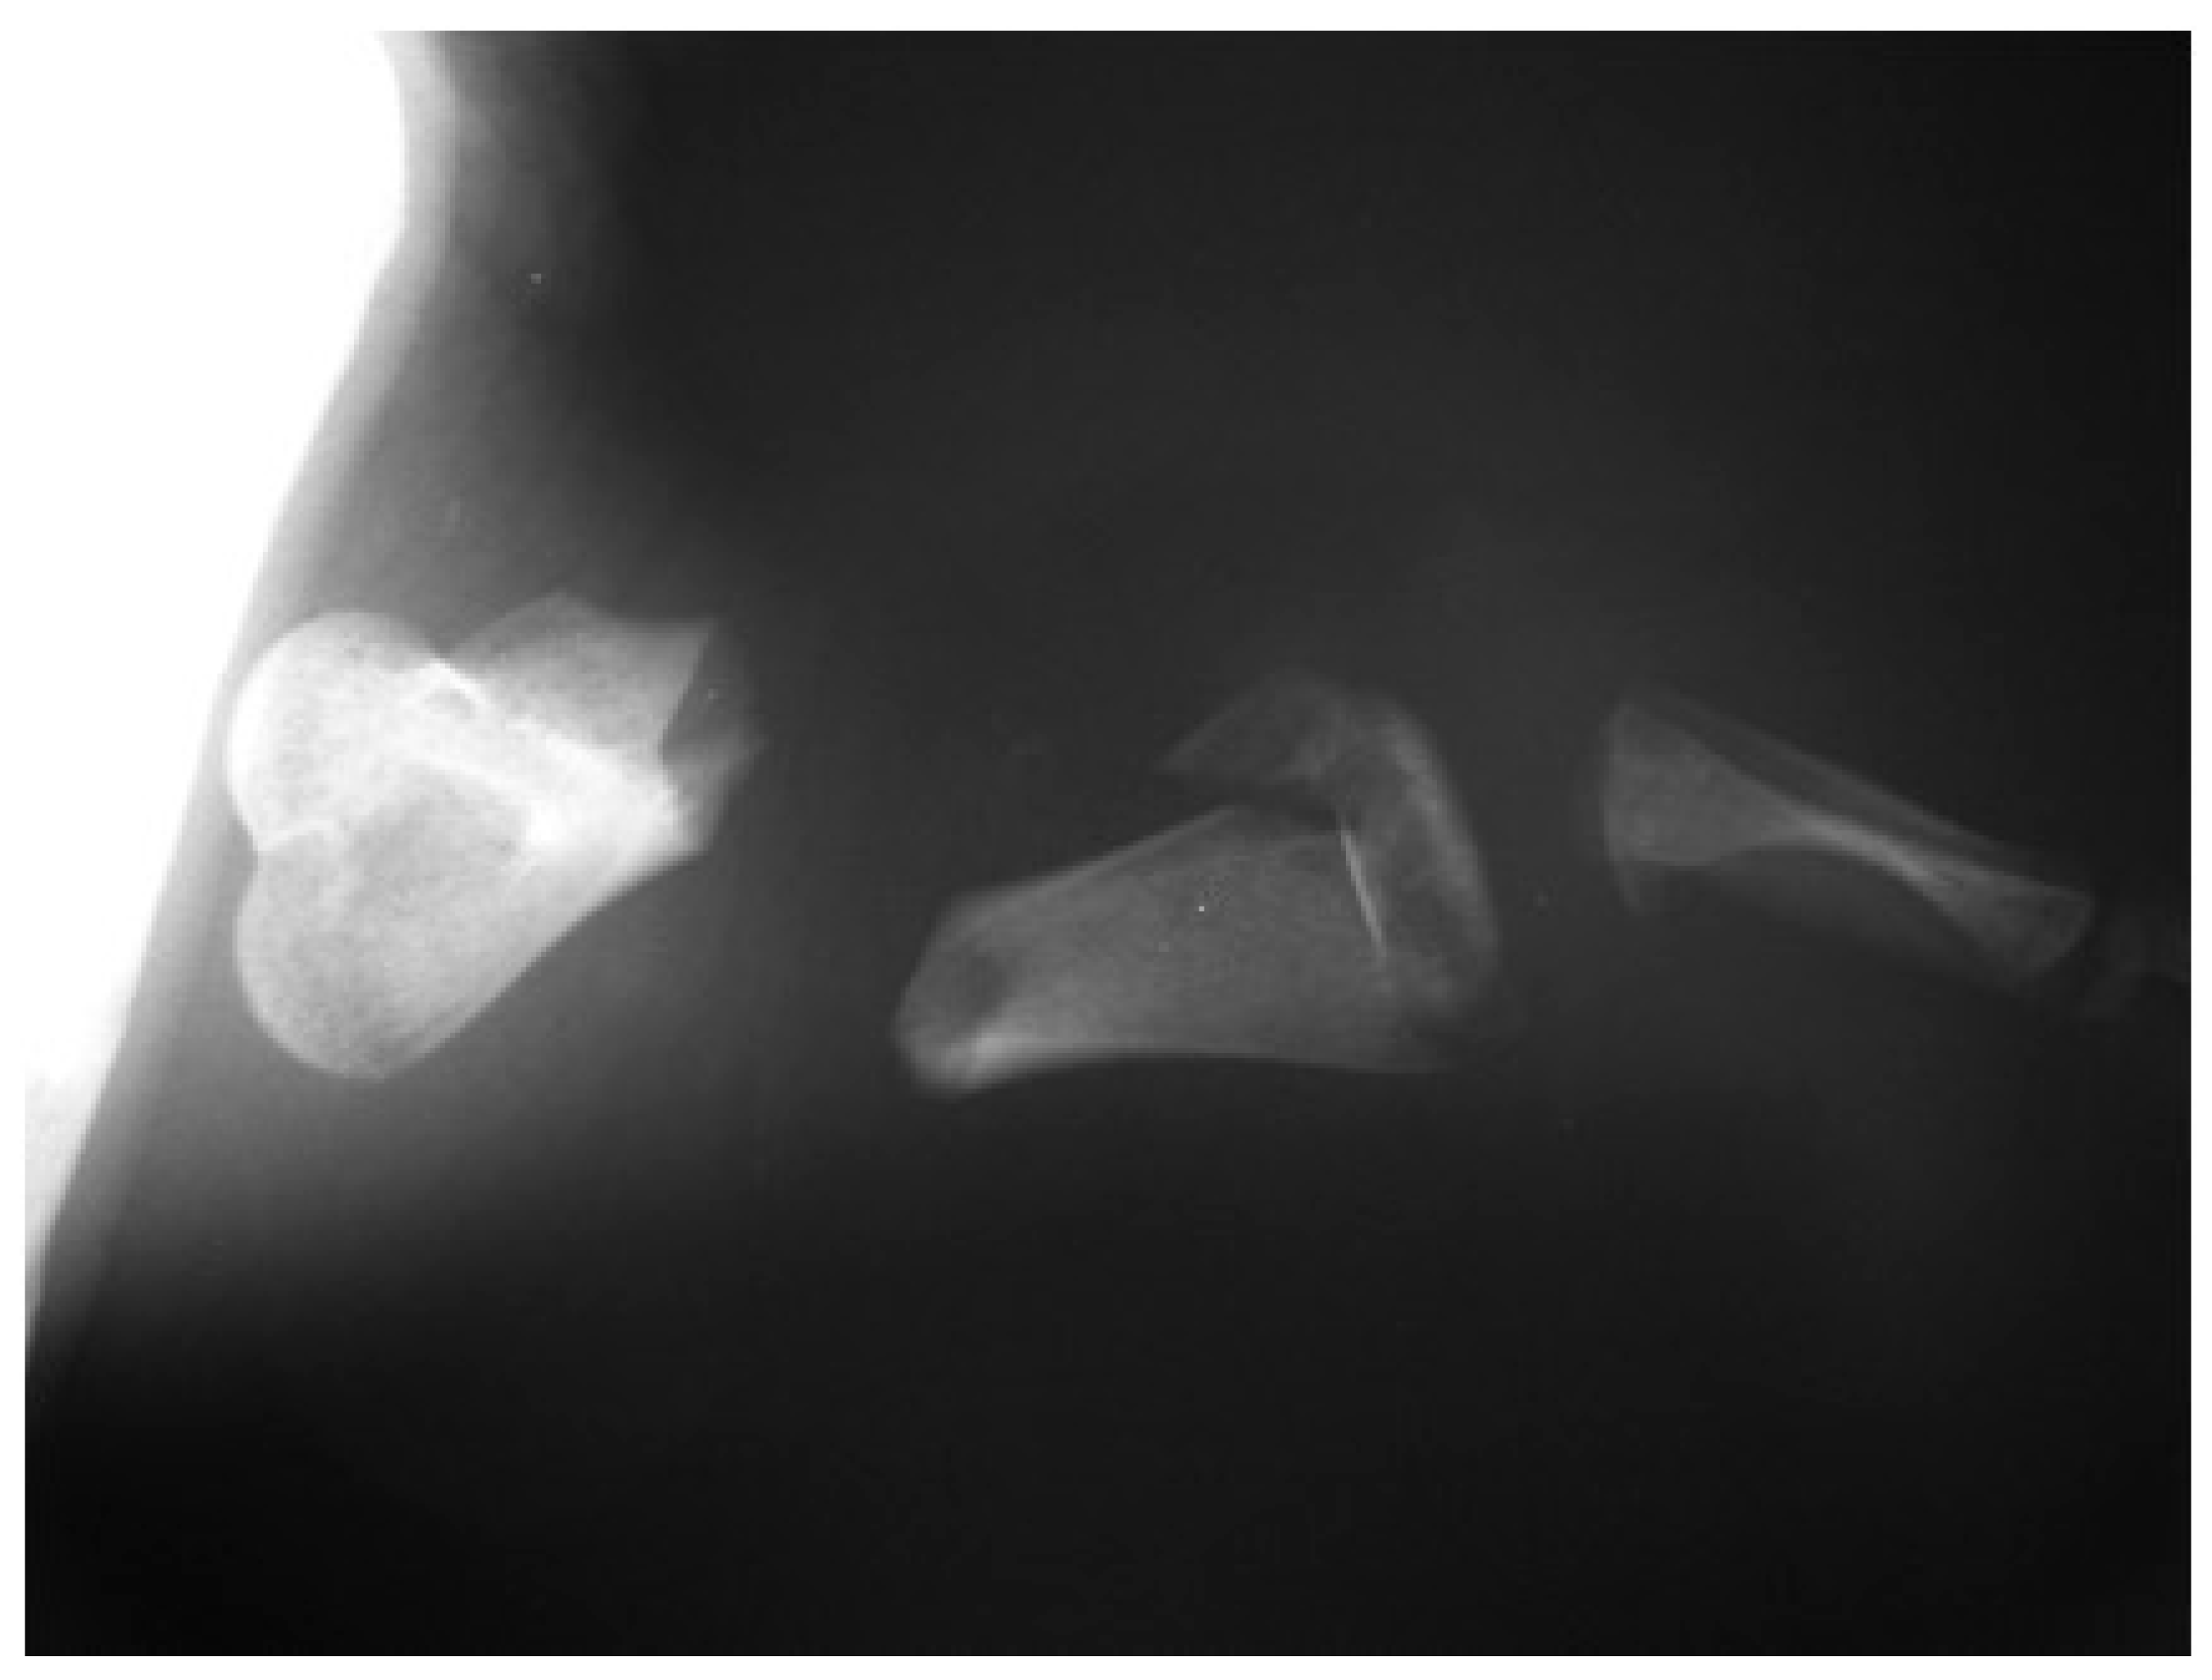

The post-operative radiographic examination confirmed the correct reduction of the diaphyseal fracture, bone realignment, and the good fixation of the detached distal epiphyseal stump (Figure 3). Fifty days later, the X-ray follow-up showed persistent stability of the joint and bone sclerosis, near the diaphyseal fracture site. After 70 days, the turtle could swim and move around comfortably; radiographic examination showed a better filling of the diaphyseal fracture line and almost complete repair of the epiphysis (Figure 4). Four months after surgery, the animal was in good general condition and had recovered the right front flipper’s normal function. Radiography showed a complete repair of the epiphyseal fracture and remodeling of the normal bone architecture, while the diaphyseal fracture still lacked unifying bone callus tissue (Figure 5). After one year, the flipper showed complete clinical recovery without signs of pain, and radiologically the fracture site was fixed, showing signs of remodeling of the fracture stumps, areas of thickened fibrous tissue, but still no appreciable unifying bone callus (Figure 6a). The good positioning and tightness of the means of fixation were radiologically confirmed, but the surrounding bone reabsorption and decalcification processes were evident. Removal of the intramedullary pins was deemed necessary. Radiograms performed after removal of the pins showed the presence of calcified sites within the tissue interposed between the two bone stumps (Figure 6b). Two years after the procedure, radiographic follow-up demonstrated a better filling of the fracture line and further remodeling of the stump margins (Figure 7).

Figure 5. Postoperative checkup at four month: Caudocranial view of the anterior right flipper showed a complete repair of the epiphyseal fracture while the diaphyseal fracture still lacked unifying callus tissue.